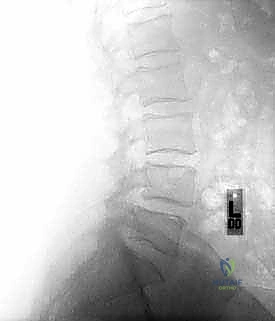

* الأشعة السينية (X-rays): خاصة الصور الديناميكية (أثناء الانحناء للأمام والخلف) لتقييم درجة عدم الاستقرار الميكانيكي والانزلاق.

* التصوير بالرنين المغناطيسي (MRI): المعيار الذهبي لتقييم الأنسجة الرخوة، ورؤية الأقراص الغضروفية، والأعصاب، والحبل الشوكي، وتحديد مكان الانضغاط بدقة متناهية.

* التصوير المقطعي المحوسب (CT Scan): يوفر صوراً ثلاثية الأبعاد للعظام، وهو ضروري جداً للتخطيط الجراحي الدقيق وتحديد أحجام المسامير المناسبة لكل سويقة فقارية.